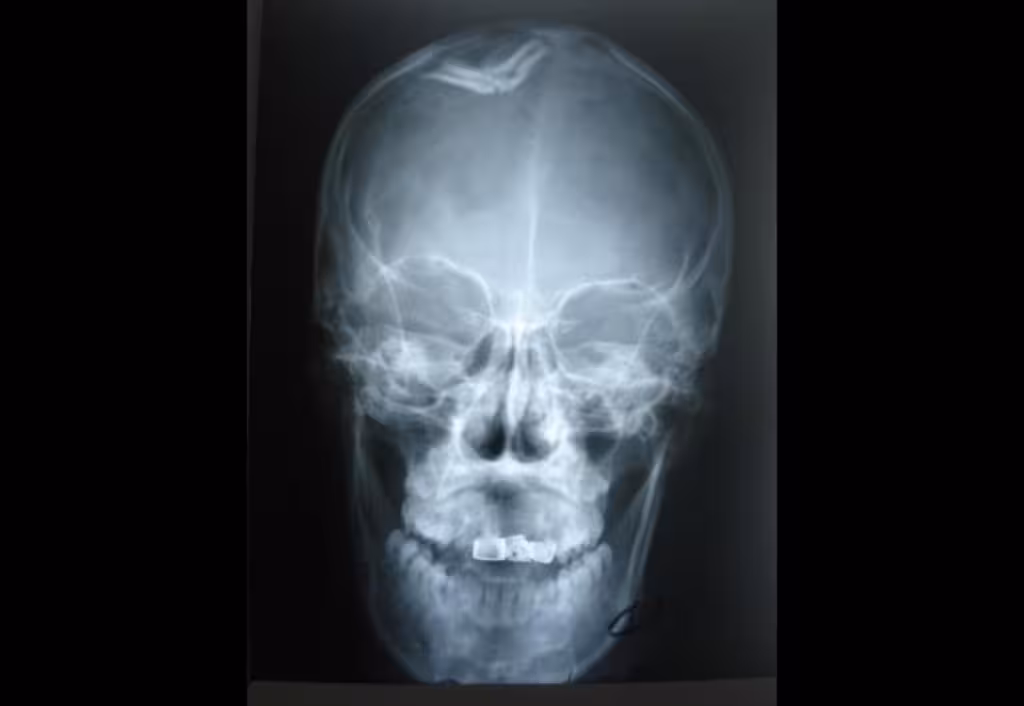

«Дев’ятого січня мешканцю Теребовлянщини стало погано, дружина викликала швидку. Рентген показав, що у нього крововилив та перелом черепа. Чоловіка госпіталізували у реанімаційне відділення. Встановили працівники поліції особу дебошира — це раніше судимий уродженець Закарпаття, 1993 року народження. Він притягувався до відповідальності за тілесні ушкодження», — додали в поліції